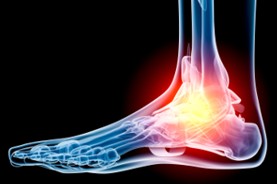

The Foot Institute is an association of Calgary Doctors specializing in the medical treatment of the foot and ankle, and is one of the largest groups of foot specialists in Alberta.

The Calgary Foot Institute is dedicated to the medical and surgical treatment of the foot. Our mandate is to provide the best possible medical, surgical and preventative treatment available for our patients. We do this by providing well-trained Doctors who are committed to treat and prevent all types of foot pain, biomechanical disorders, as well as all other problems relating to the feet.

At the Calgary Foot Institute, our Doctors are trained to specifically treat problems associated with your feet or ankles. Below are several of the most common problems that we see on a day to day basis: